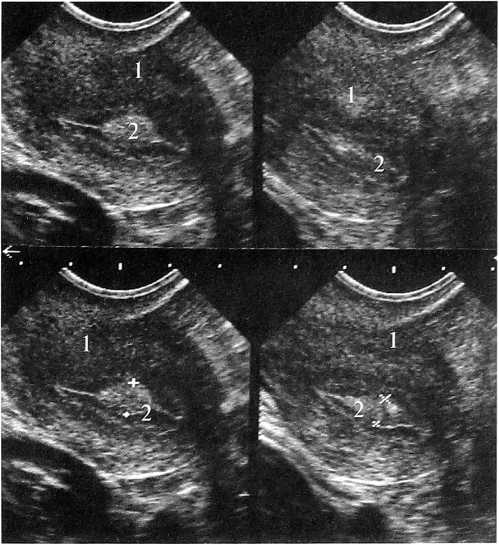

Рис. 4а. Рис. 4б.

Рис. 4а. Больная К. 35 лет. 11 день МЦ.

Два «замороженных» изображения матки до введения окситоцина. ЛУГ в эндометрии в середине полости матки. Продольное ТВ-сканирование: 1 — матка, 2 — М-эхо с ЛУГ

Рис. 46.

Два изображения матки после начала действия окситоцина. Изменение формы ЛУГ в эндометрии при сокращении стенок матки. Продольное ТВ-сканирование: 1 — матка, 2 - М-эхо с ЛУГ

При проведении ФФДП (рис. 4, 5) на фоне сокращения стенок матки отмечалось изменение формы образования из округлой — в удлиненную, с наличием заострений в месте перехода в неизмененный центральный отдел эндометрия, представляющий собой место соприкосновения передней и задней стенок полости матки (рис. 1, 2, 4, 5). У пациенток этой группы была выявлена тенденция к повышению пролактина, который на 3 день МЦ составлял от 344 до 620 мМЕ/л, ФСГ и ЛГ соответствовали верхней границе нормы, Е2 и прогестерон были не изменены. При проведении гистологического исследования эндометрия на 20—25 день МЦ были получены следующие данные: эндометрий пролиферативной или секреторной фаз с расширением просвета желез разной степени выраженности (железистая гиперплазия), в ряде случаев с наличием кистозно-расширенных желез (железисто-кистозная гиперплазия). В цитограмме аспирата диагностированы крупные пласты эндометрия пролиферативного или секреторного типа (иногда с множеством желез), без признаков атипии. При проведении ГС в полости матки определялся одиночный участок эндометрия в виде неравномерно утолщенной складки, выступа бледно-розового или красного цвета — зона локальной, очаговой функциональной гиперплазии.

Рис. 5а. Рис. 5б.

Рис. 5. Больная Т. 30 лет. 11 день МЦ.

Эндометрий соответствует пролиферативной фазе, с выраженным влиянием секреторной фазы, большой ЛУГ в середине полости матки. Продольное ТВ-сканирование: 1 — матка, 2 — М-эхо с ЛУГ; ФФДП а) — до введения окситоцина; б) — после введения окситоцина (УЗ картина напоминает одиночный крупный полип эндометрия)